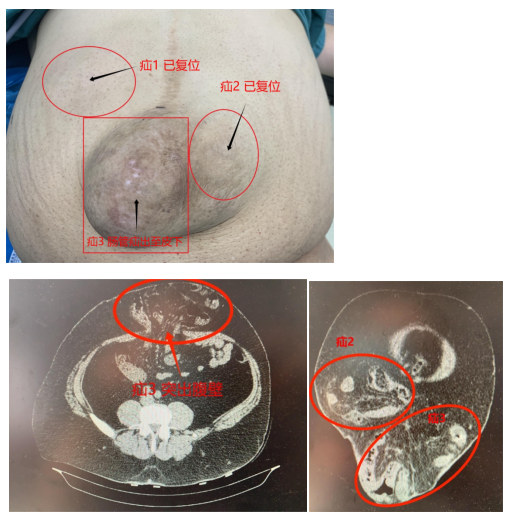

近期开展的疑难手术如下(文末有详细链接查看):外国友人多发巨大切口疝腔镜复合补片修补术(图1-3)、强直性脊柱炎患者腹股沟疝腹腔镜无张力疝修补术(TAPP)(图4)、复发性造瘘口旁疝杂交疝修补术、疑难巨大嵌顿脐疝腹腔镜腹膜外无张力疝修补术(TEP)、反流性食管炎合并食管裂孔疝补片修补并胃底折叠术、小儿疝单孔腹腔镜疝囊高位结扎术等。

图1-3